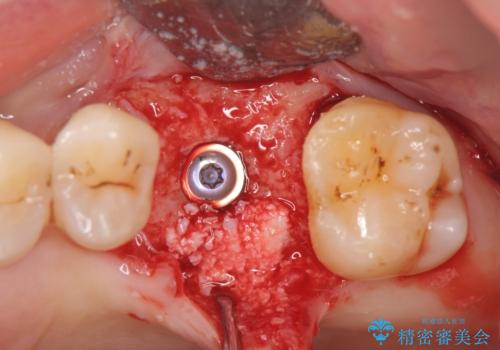

- 44万円(インプラント・チタンカスタムアバットメント・ジルコニアクラウン・仮歯)費用は治療当時の料金となります

歯が割れるほどの咬合力が強い方でしたので、3本の歯を2本で支えるブリッジではなく、咬合負担能力の増えるインプラント治療にメリットが大きいと言えます。